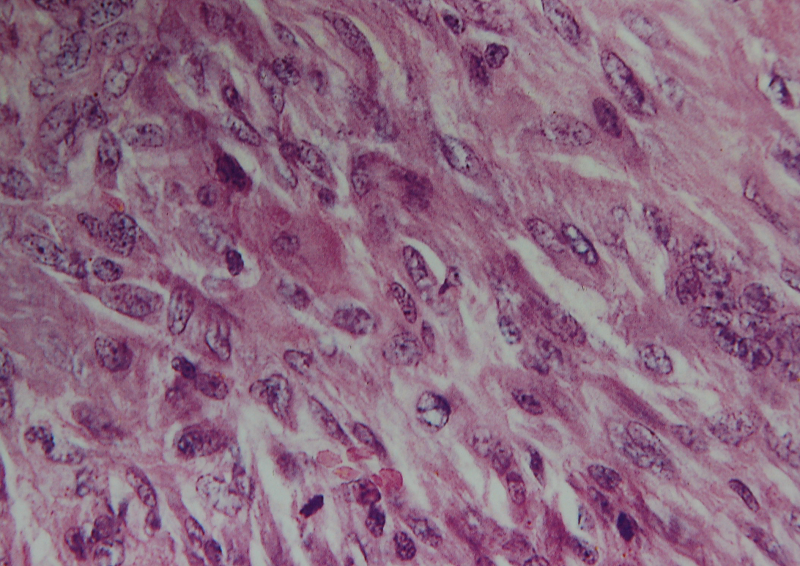

2.镜下

组织学特征性改变为圆形、卵圆形、多角形或梭形的单核基质细胞,以及均匀分布其中的破骨细胞样巨细胞。这种巨细胞体积可以很大,核的数量可达到50~100个,基质细胞的核与巨细胞的核形态相似,染色质疏松,1~2个小核仁,胞质界限不清,细胞间含有少量 胶原,核分裂象易见,每10个高倍视野可见2~20个不等,但无病理性核分裂。

大的特征性破骨细胞样巨细胞并非肿瘤细胞这一观点现在已基本被接受,作为肿瘤性成分的单核基质细胞被认为是来源于原始间充质细胞(primitive mesenchymal stromal),这种单核细胞在瘤组织中数量较少,其表达的RANKL可刺激破骨细胞前体细胞向破骨细胞转化和成熟。

在具备上述基本特征的基础上,骨巨细胞瘤可分为多种类型。在一些病例,单核细胞形态更趋向于梭形,并可以排列成车辐状结构。通常情况下,可存在少量泡沫细胞,在少数病例,由于大量泡沫细胞的存在,产生类似纤维组织细胞瘤的改变。在大约10%伴发继发性动脉瘤样骨囊肿的病例中,可出现纤维化区域。肿瘤中可有小灶性的新生骨形成,特别是在发生病理性骨折或骨活检术后的病例中。当病变扩展至软组织中或转移至肺组织中时,组织学特征与原发灶相同,并且经常可以见到外周反应性骨壳。在1/3的病例中,一个显著的特征是存在血管内瘤栓,特别是在瘤体的周边部,但没有特殊的预后价值。在体积较大的病变中肿瘤坏死亦很常见。

图 6 组织学表现

图 19 组织学特点:瘤细胞呈梭形,似肉瘤样,可见较多核分裂。